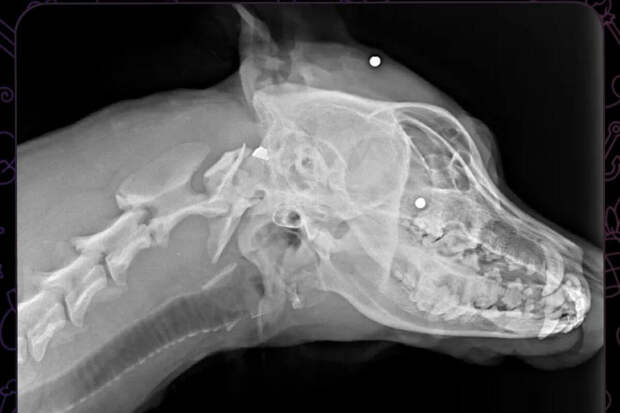

Инцидент произошел в поселке Новознаменском - местные жители обнаружили на остановке собаку с ранениями. Предположительно, ее обстреляли из пневматического оружия. Рентген показал, что пули застряли по всему телу животного.